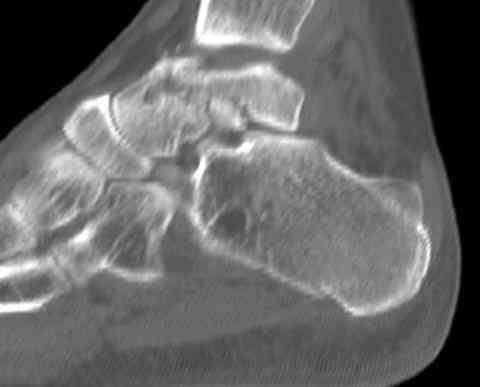

Для оценки состояния нужны дополнительные исследования, например Canale или Broden ренгенограммы и Компьютерная томография.

На ренгенограмме не уловил многоскольчатость тарана, чтобы доказать, конечно, можно было исследовать на КТ, потом КТ дает ориентацию фрагментов.

Два фрагмента суставной поверхности тарана можно восстановить боковой компрессией шурупами и дополнительно костная пластика.

(кстати, на нашем случае была применена костная пластика-allograft crouton для заполнения дефектов)